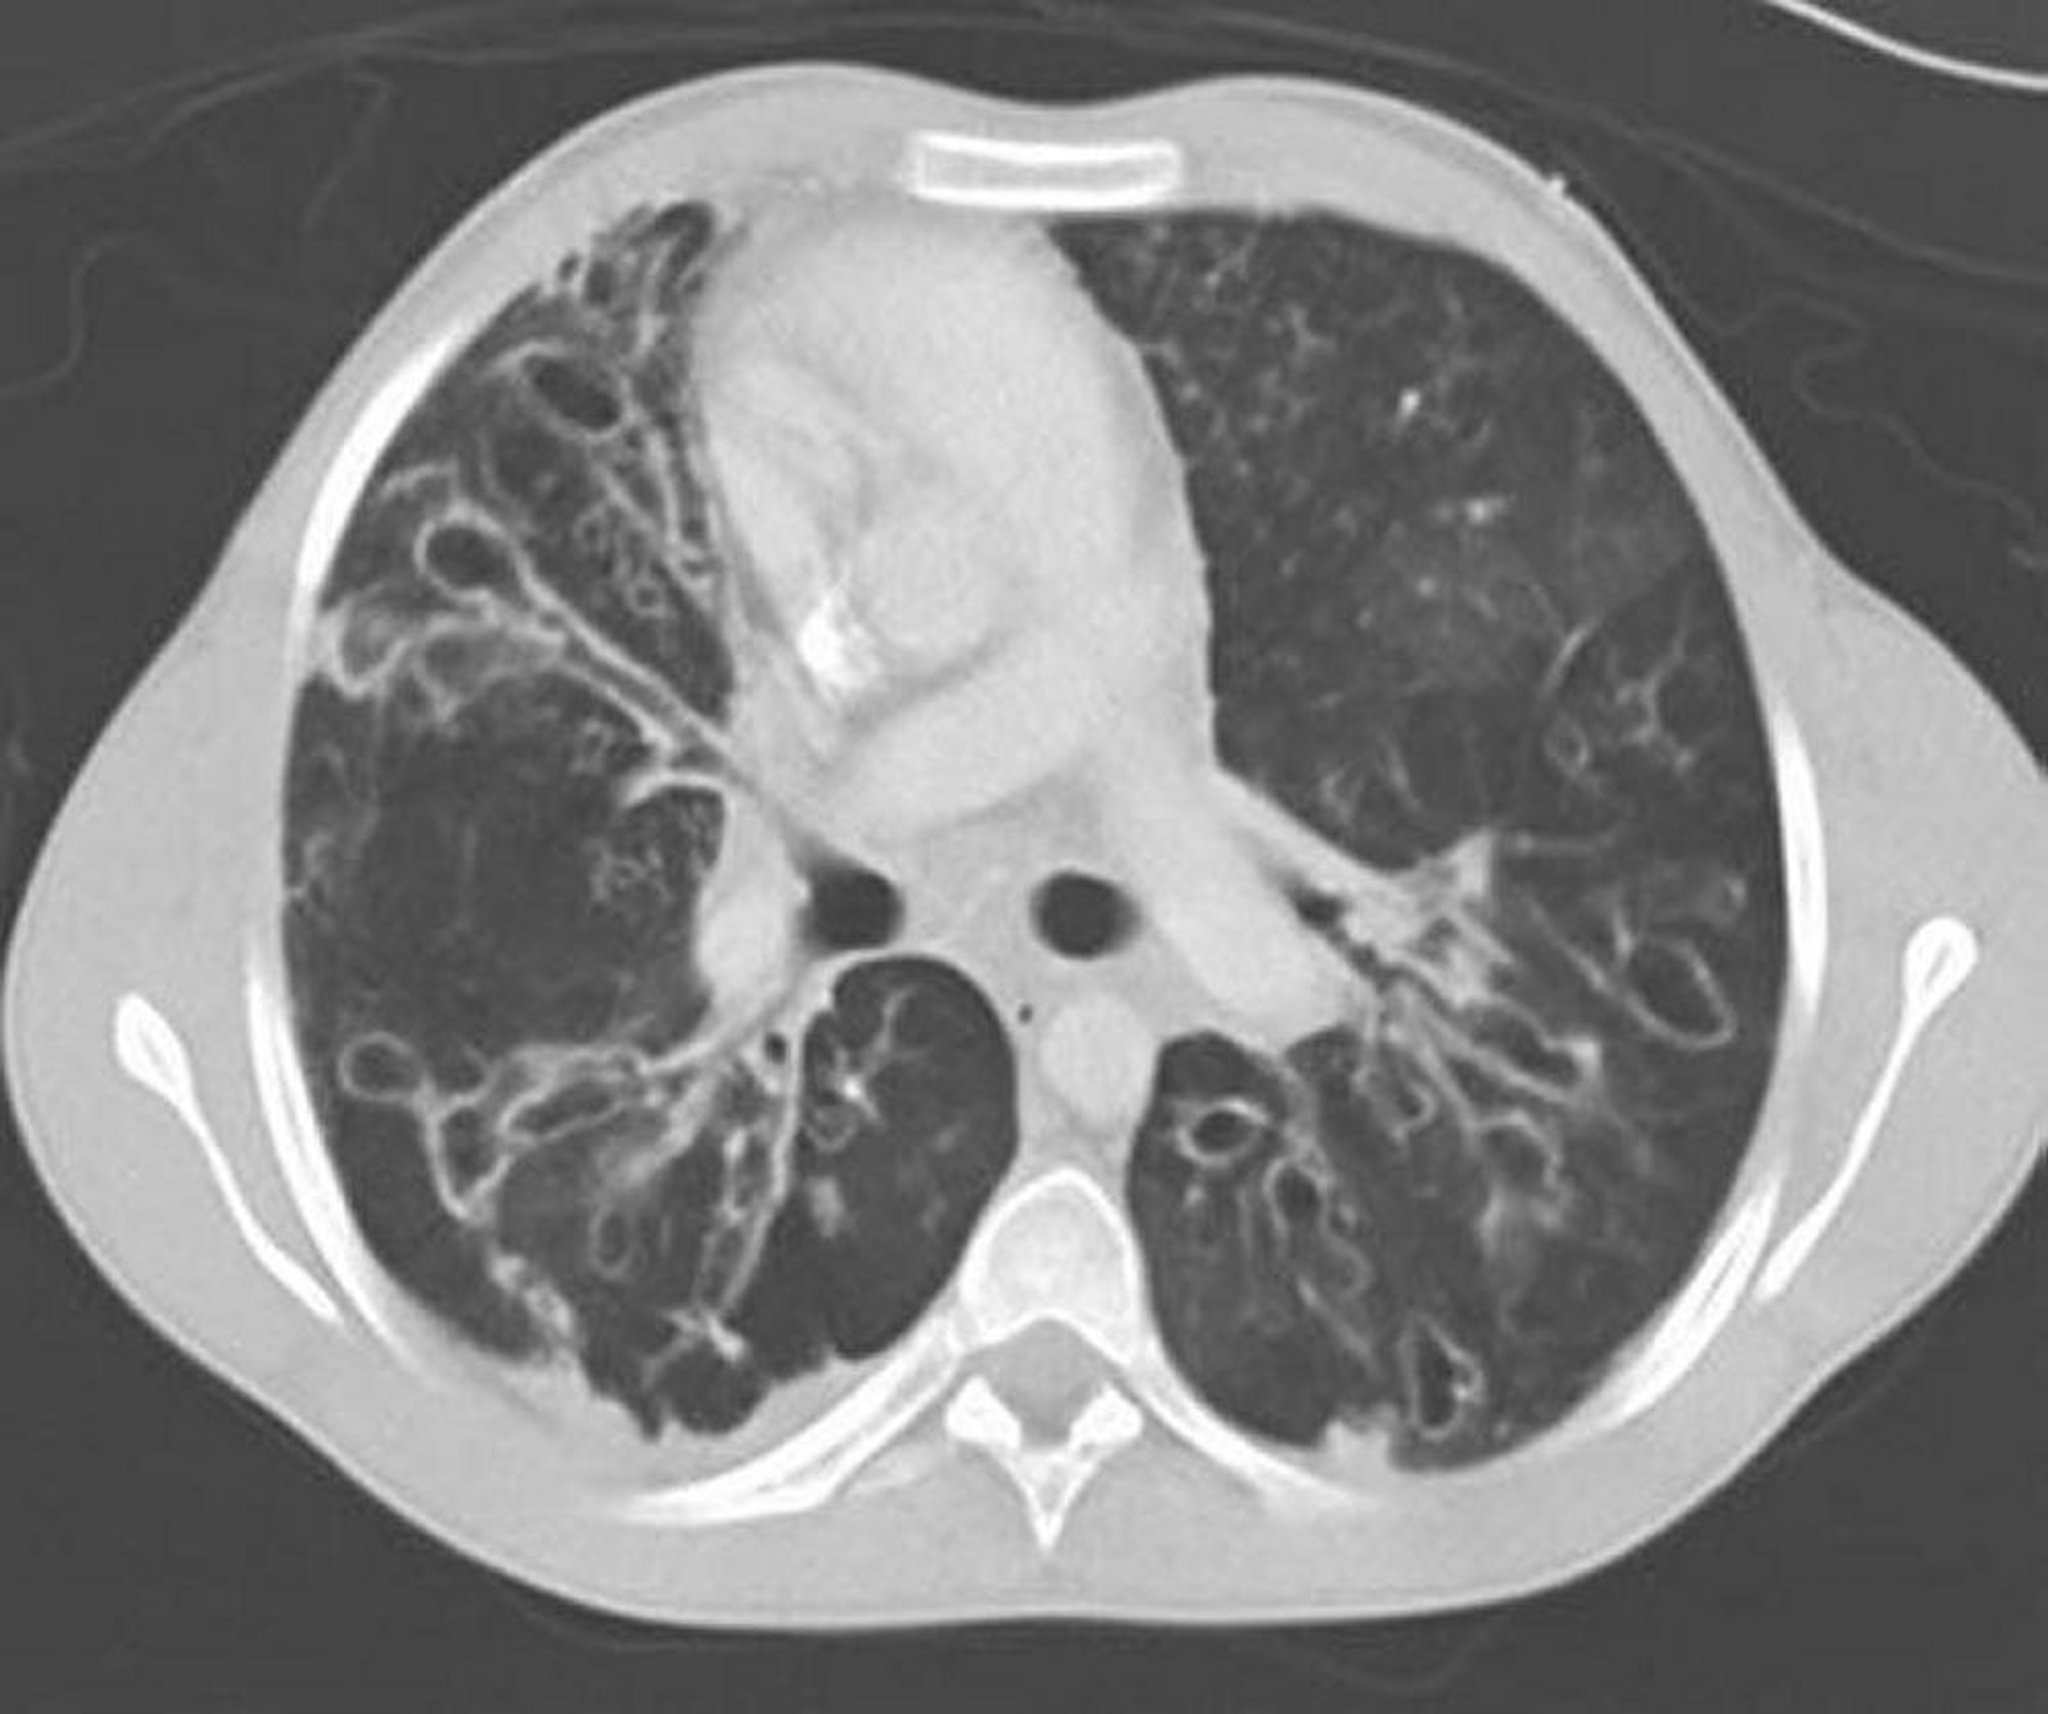

Allergic Bronchopulmonary Aspergillosis (Bronchiectasis)

A contrast-enhanced CT of the chest shows severe bronchiectasis in the midlung zones with grossly dilated and ectatic airways and cystic changes. Airway ectasia dis characterized by a ratio of airway to adjacent vessel > 1.

By permission of the publisher. From Coakley R, Boucher R, Fiel S, et al. In Bone's Atlas of Pulmonary and Critical Care Medicine. Edited by J Crapo. Philadelphia, Current Medicine, 2005.